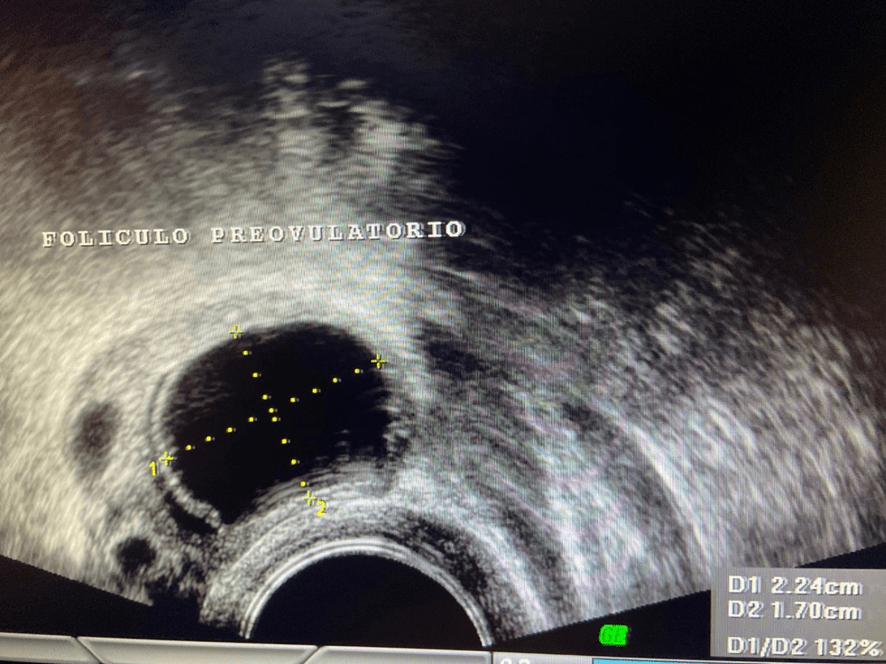

Una vez que el folículo maduro se ha roto -ha estallado- y se ha expulsado el óvulo que contenía (ovulación) la capsula del folículo adquiere un aspecto rugoso, grueso e irregular al que llamamos “cuerpo lúteo”. En su interior, frecuentemente, se produce un acúmulo de sangre por lo que también se le conoce como cuerpo lúteo hemorrágico.

Además de estrógenos, este cuerpo lúteo empieza a segregar una hormona llamada Progesterona; la cual, es la causante de que el endometrio- que antes de la ovulación era proliferativo y con sus tres capas bien definidas- se transforme en un endometrio grueso, espeso e irregular. Se le conoce como “endometrio secretor”.

Una de las formas de identificar al cuerpo lúteo es a través de la imagen ecográfica que obtenemos cuando se le aplica el Eco Doppler Color y aparece el típico anillo de colores que lo rodea.